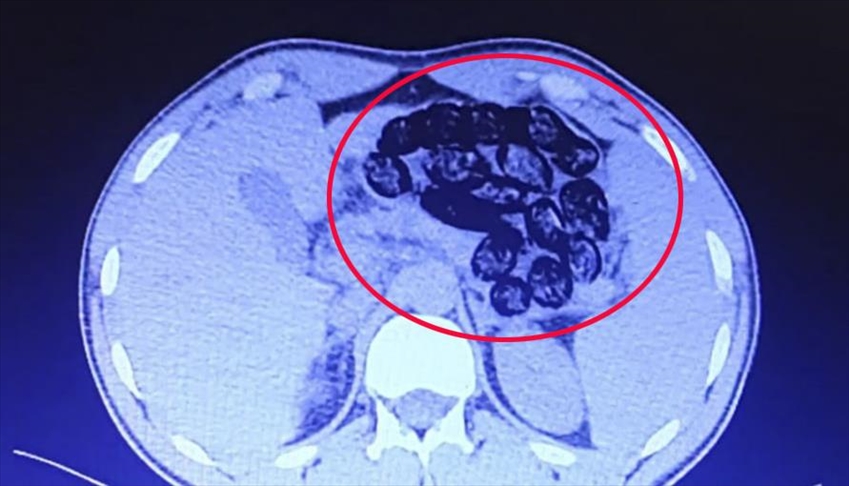

پلیس ترکیه دو شهروند ایرانی که 920 گرم مواد مخدر را در قالب 103 بسته در معده خود حمل میکردند، دستگیر کرد.

اداره امنیت استان وان ترکیه با انتشار اطلاعیهای اعلام کرد پلیس این استان دو شهروند ایرانی که 920 گرم مواد مخدر را در قالب 103 بسته در معده خود حمل میکردند، دستگیر کرده است.

پلیس ترکیه پس از دستگیری این افراد، آنها را به بیمارستان منتقل کرده و 920 گرم مواد مخدر موجود در معده آنها خارج شد.